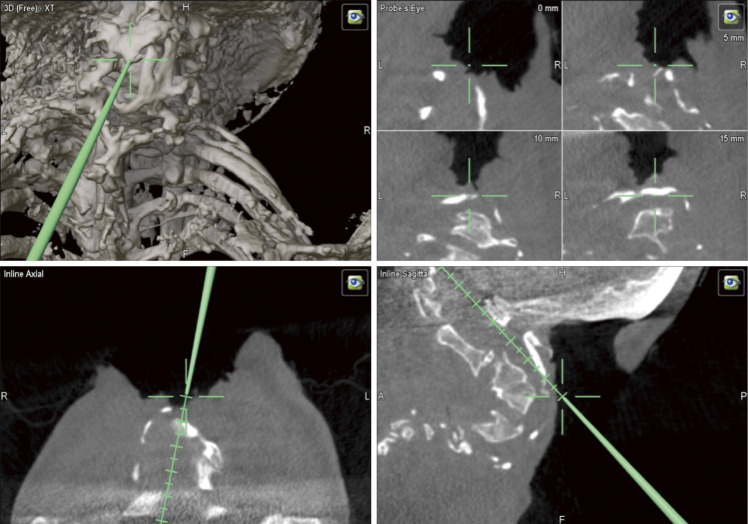

Treating Severe Cervical Deformity in Neurofibromatosis 1 with a Posterior Fibula Graft from Occiput to Thoracic Spine: A Case Report.

用枕骨到胸椎的后腓骨移植治疗神经纤维瘤病 1 的严重颈椎畸形:病例报告。